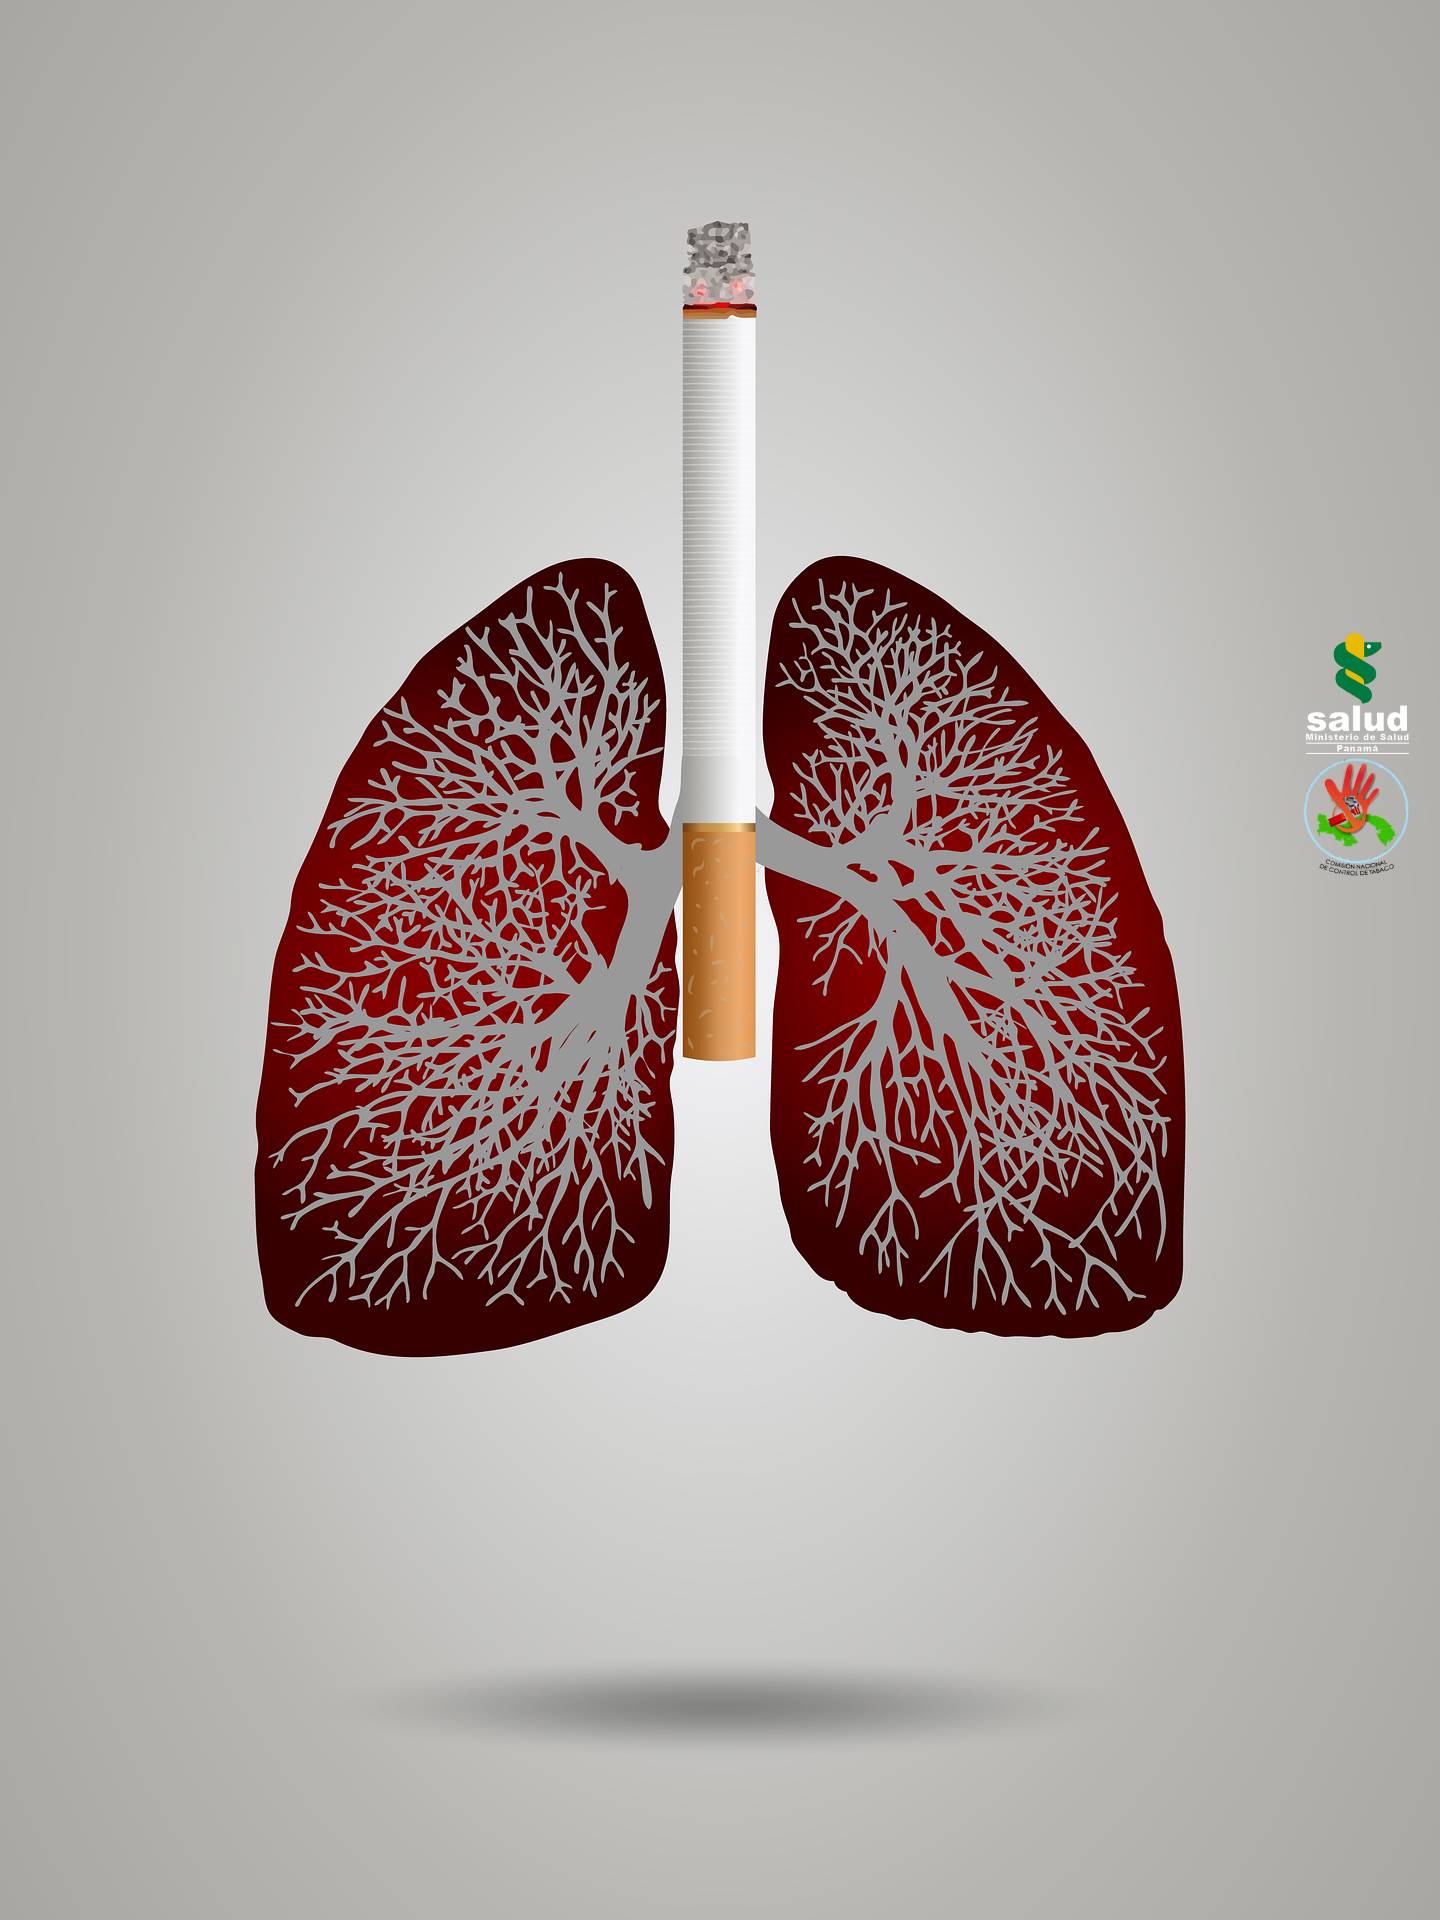

Tabaco y enfermedad pulmonar

El humo del tabaco afecta a los pulmones